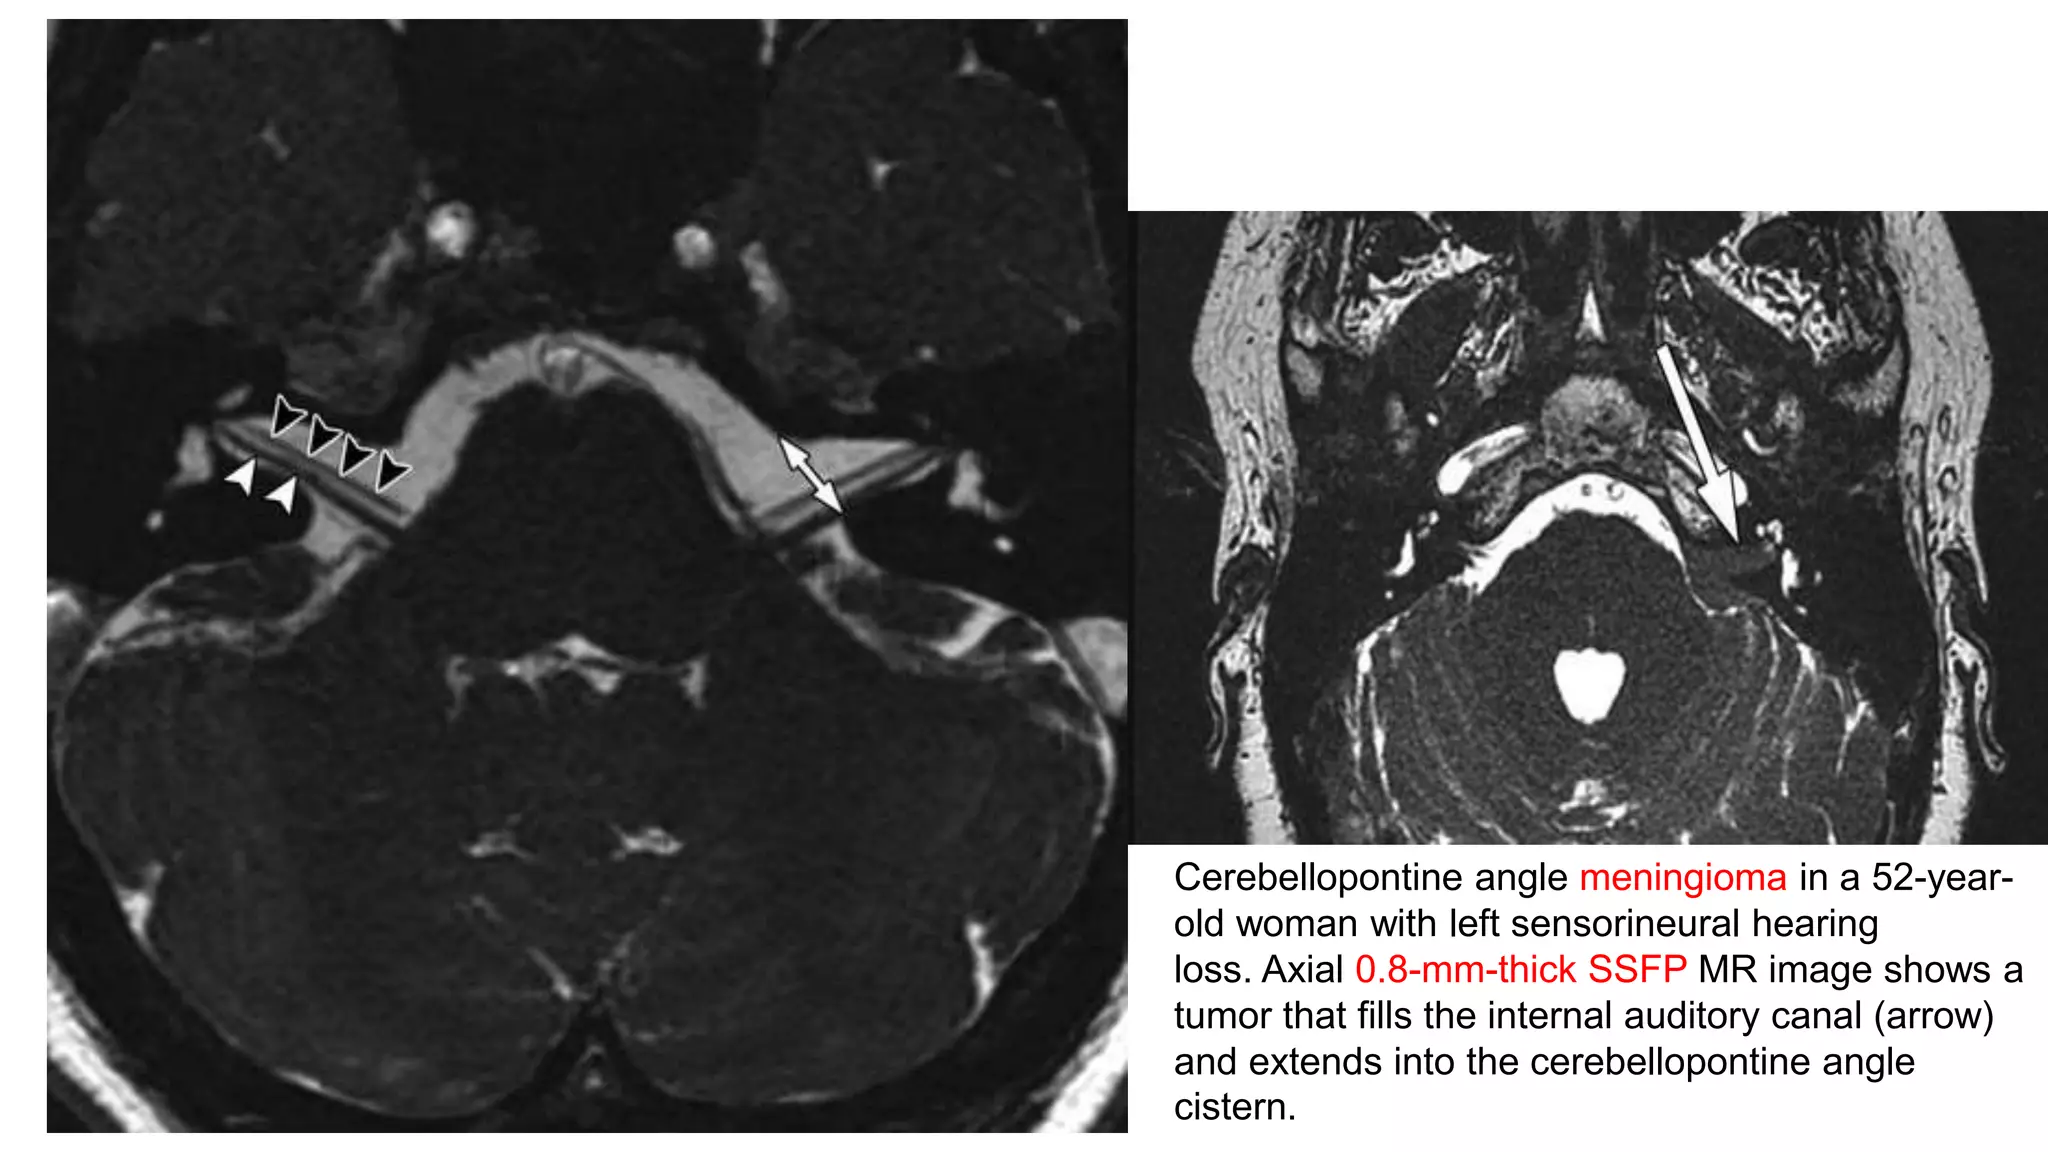

Cerebellopontine angle meningioma in a 52-year-

old woman with left sensorineural hearing

loss. Axial 0.8-mm-thick SSFP MR image shows a

tumor that fills the internal auditory canal (arrow)

and extends into the cerebellopontine angle

cistern.

Meningioma

• Meningiomas are solid, well-

circumscribed, and slow-growing tumors

that are composed of neoplastic

meningothelial cells originating from the

arachnoid layer of the meninges with a

broad attachment to the adjacent dura.

• Meningiomas are second most frequent

CPA tumor

• Hypointense on CISS sequence

obliterating the vestibulocochlear nerve

• Meningiomas show homogenous

enhancement on postcontrast T1WI

Cerebellopontine angle meningiomain a 52-year- old woman with left sensorineural hearing loss. Axial 0.8-mm-thick SSFP MR image shows a tumor that fills the internal auditory canal (arrow) and extends into the cerebellopontine angle cistern.

Meningioma • Meningiomas aresolid, well- circumscribed, and slow-growing tumors that are composed of neoplastic meningothelial cells originating from the arachnoid layer of the meninges with a broad attachment to the adjacent dura. • Meningiomas are second most frequent CPA tumor • Hypointense on CISS sequence obliterating the vestibulocochlear nerve • Meningiomas show homogenous enhancement on postcontrast T1WI